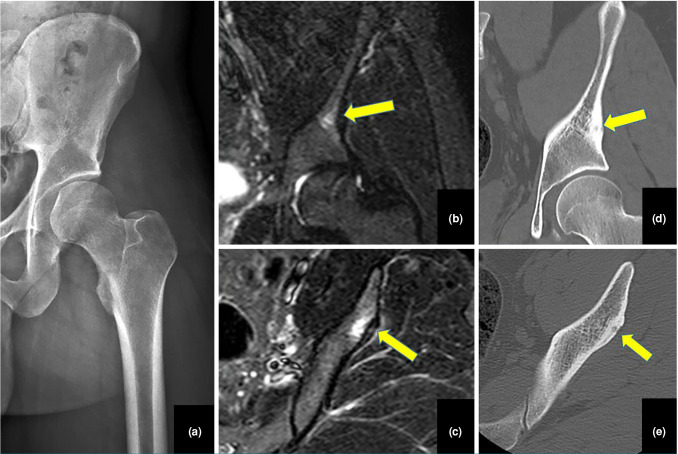

Objectives: This study aims to evaluate delayed diagnosis of osteoid osteoma (OO) in pediatric patients with hip pain and to identify the diagnostic challenges and errors encountered during this period.

Results: The median time from symptom onset to diagnosis was 12 months. Right-sided involvement was observed in 61.1% of cases. The most common lesion location was the femoral neck (61.1%), and 66.7% of cases had intra-articular lesions. A limping gait was observed in 61.1% of patients. Additionally, 33.3% of cases reported atrophy of the thigh muscles and/or lower extremities. Night pain was present in 83.3% of cases. A total of 72.2% of cases had a diagnostic delay exceeding six months. Half (50%) of the patients required more than five visits to healthcare providers before receiving an accurate diagnosis.

Conclusion: The diagnostic delays for OO located in the hip region can be seen in among children and young adults, primarily due to misdiagnosis and reliance on inconclusive initial imaging findings. To minimize such delays, clinicians should maintain a high index of suspicion, particularly in patients with persistent, unexplained hip pain, and consider imaging studies. Pain lasting over three weeks warrants further diagnostic evaluation in this patient group.